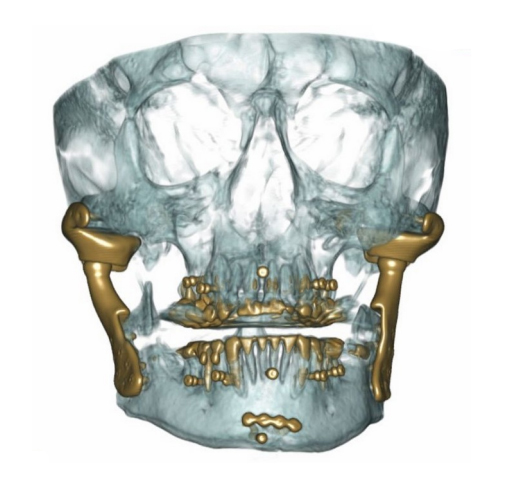

Durante questa full-immersion i partecipanti apprenderanno l’anatomia dell’ATM, riassumeranno le linee guida cliniche della DC/TMD, impareranno il corretto esame obiettivo da eseguire sul paziente DTM, leggeranno le risonanze magnetiche, conosceranno l’ “HOW TO BASIC” per la corretta gestione del paziente disfunzionale. Il tutto correlato e delucidato alla luce di numerosi casi clinici.

- Indicazioni cliniche per la Chirurgia dell’ATM e descrizione di casi clinici